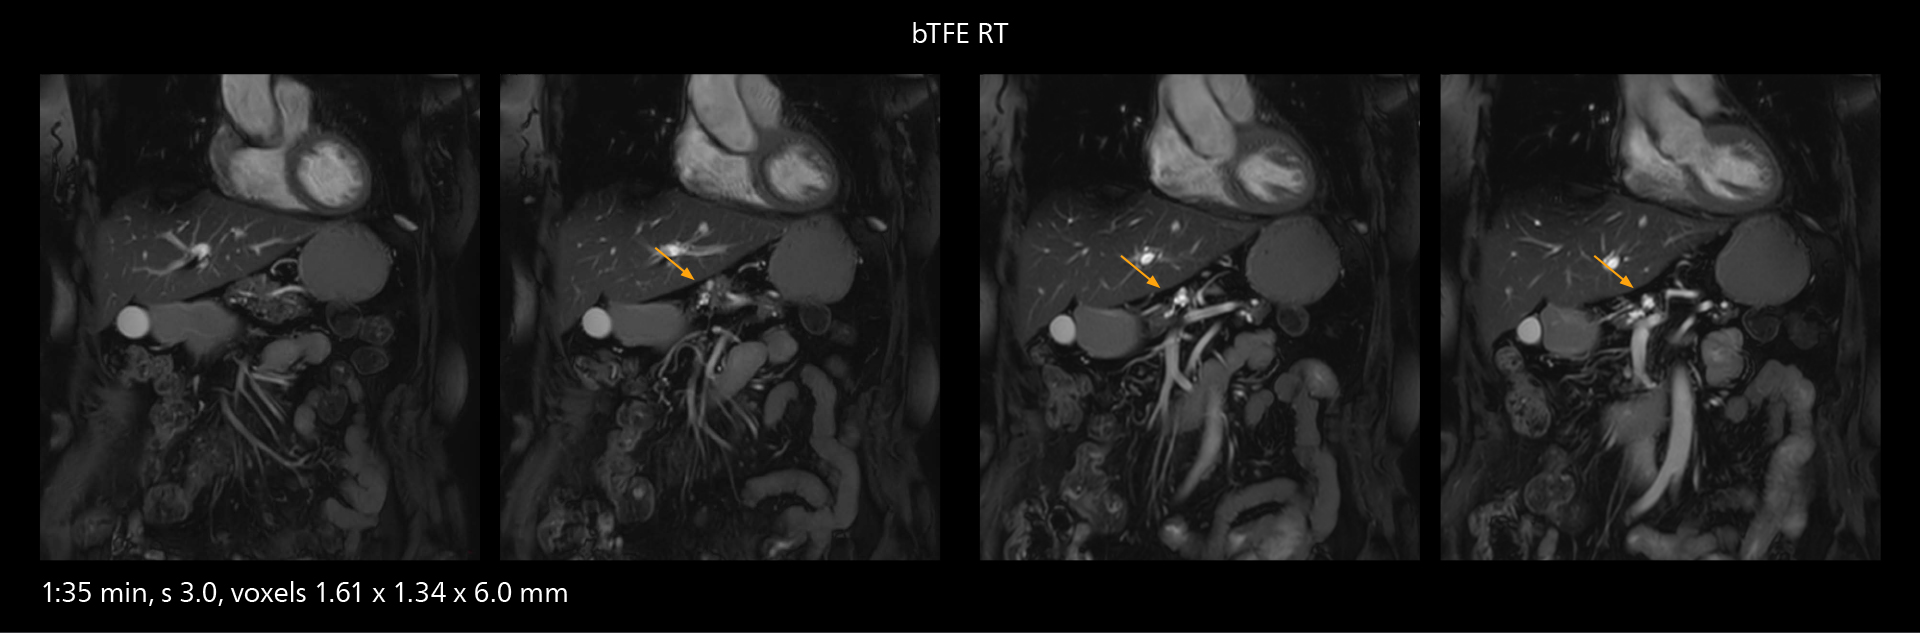

The high performance of the Vega HP gradients is particularly impressive in DWI. “The Vega HP gradients enable us to scan faster and use b-values as high as 2000, for example in prostate DWI and in DWIBS, which provides image quality that is remarkably improved over the previous system and we are able to more easily see lesions.”

Examples of prostate imaging showing faster scan times and improved resolution illustrate the power of SmartPath to Elition X in this case of prostate cancer with PI-RADS score 4.